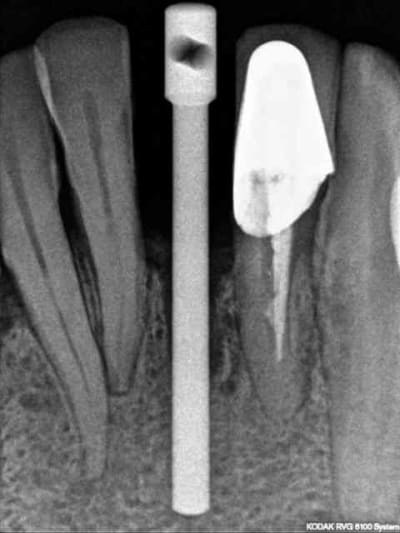

4)5) forêt pointeur (un petit coup de boule pour les kystes éventuelles et tissus mous)5

7)contrôle de l'axe

8) radio (faut dire que le couloir dans lequel on peut mettre l'implant est étroit)